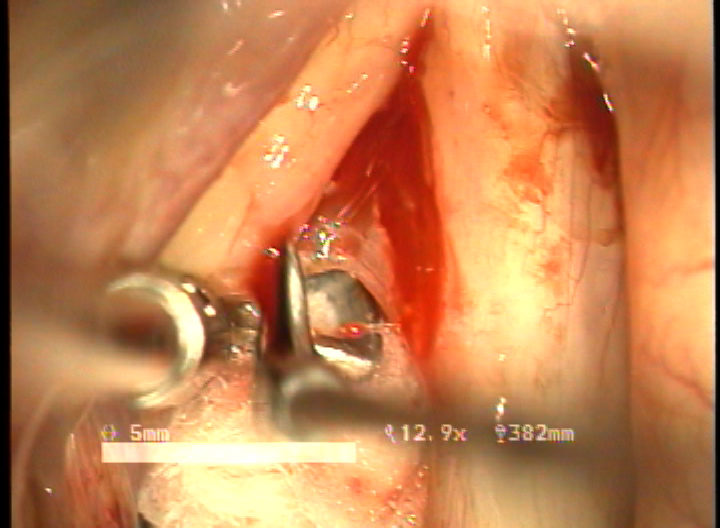

double rotational microflap laryngoplasty 수술 동영상... more >

목적 : 전성문횡격막(anterior glottic web)은 선천성이나 수술과 같은 이차적인 원인에 의해서 발생되는 난치성 후두질환이다. 또한 기존의 치료방법으로는 음성개선의 효과가 매우 낮은 결과를 얻고 있다. 이에 음성의 보존과 함께 일차적 시술로서 치료가 가능한 double rotation microflap 을 이용한 새로운 술식을 보고하며, 이술식의 치료결과와 음성학적 개선을 알아보고자 하였다.

방법 : 2006년 1월 부터 2007년 12월 까지 예송이비인후과에서 전성문횡격막으로 진단되어 double rotational microflap laryngoplasty를 시행받고 1년간 장기추적이 가능하였던 6명의 환자를 대상으로 후향적 분석을 시행하였다. 원인적인 요인과 동반질환으로는 후두유두종 술후 합병증 4례, 후두외상 1례, 폴립양성대 1례 였다. 남녀 각각 3례였으며, 평균연령은 39세 였다. 추적기간은 21.5 개월이었다. 술 후 2개월과 6개월에 음성개선에 대한 주관적인 음성평가를 시행하였으며, 음성분석검사와 후두스트로보스코피 검사를 통하여 객관적인 음성평가와 성대점막파동의 변화를 관찰하였다. 통계적 유의성은 Wilcoxon Signed Ranks Test로 검정하였다.